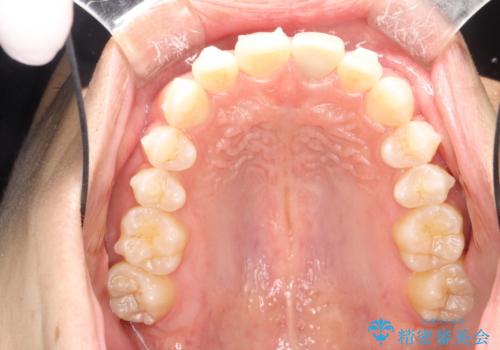

インビザラインによる矯正治療(非抜歯) 下の前歯の歯並びの改善

マウスピース枚数 初回35枚 + 追加13枚

概ね1年弱で治療が完了しました。

前歯の大きな3次元的移動を可能にするために、当院独自の工夫を随所に盛り込み、狙い通りの治療結果を得られました。